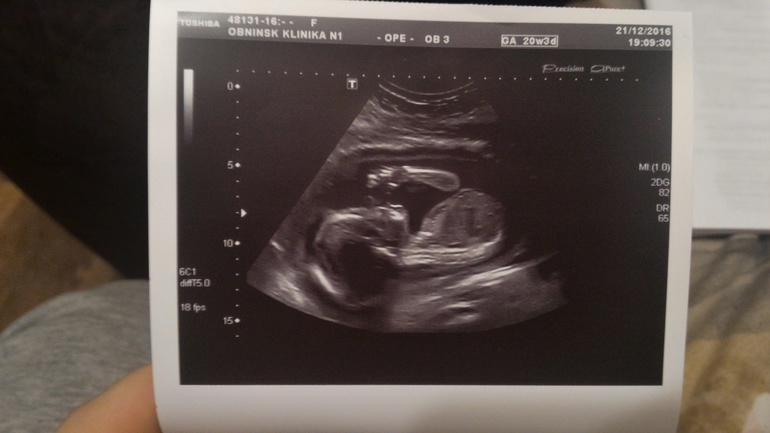

Сегодня 20 недель начались с похода на скрининг))) Нам там подтвердили сынульку, все с нами ттт хорошо, отклонений не выявлено по узи ставят 20+5 неделек) БПР -49мм , написали один живой плод в головном предлежании, плацента расположена по передней и задней стенкам левому ребру, лежим мы поперек маминого животика и я это прекрасно чувствую, буянит сын) головка справа,попка слева ))) Кол-во вод в норме шейка матки 39 мм)

В общем все хорошо и я счастлива) По состоянию все гуд, иногда только тянет связки по бокам, и то что он вытягивается когда лежит поперек доставляет дискомфорт конечно, но не такой уж и сильный) А так все замечательно)) ну и вот наш профиль и засняли нам наше достоинство)) и фотопузик)))